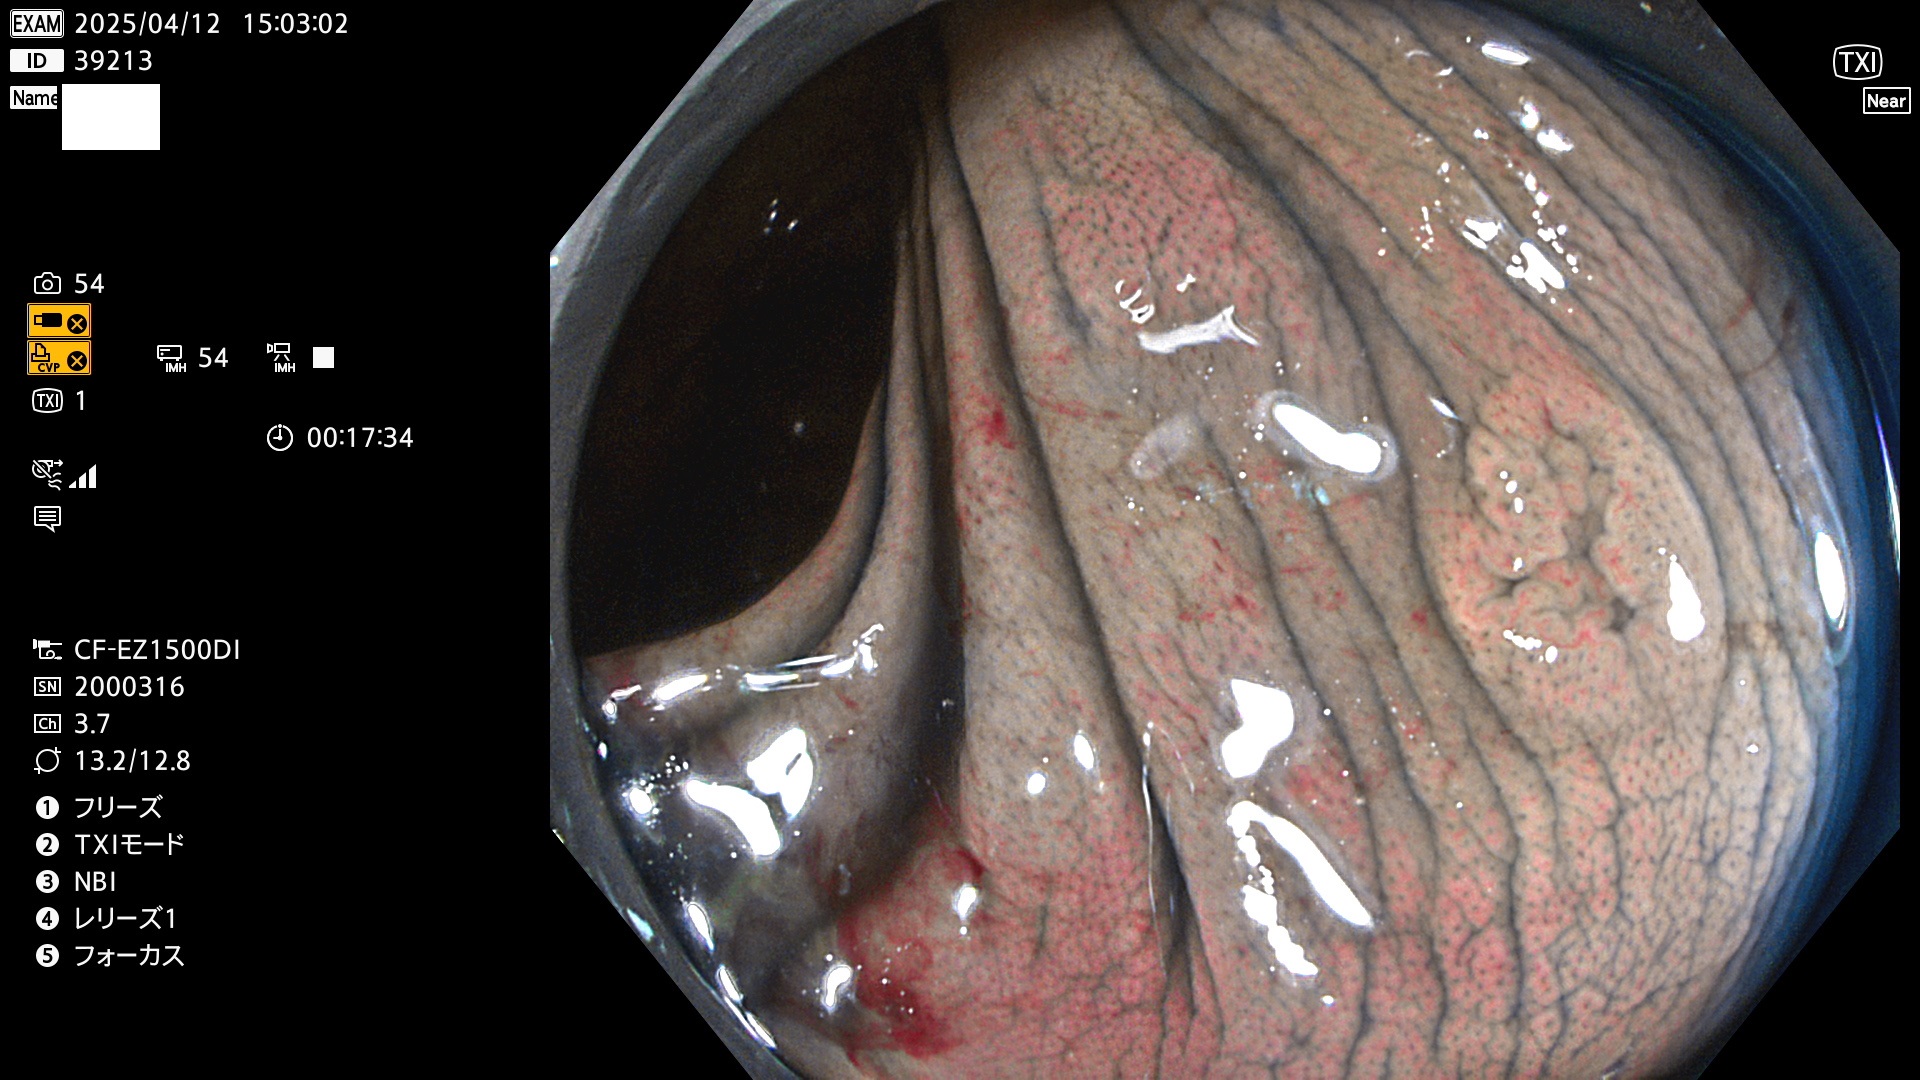

完全に平坦な物をUb、陥凹している物をUcと呼びます。Ubは認識が困難で、Ucはびらん(炎症)と紛らわしいために見落とされやすく、「内視鏡後・大腸癌」の原因になります。

抽出の対象期間 2025年4月10日〜4月13日の4日間(48件の検査)11個 (4/48=23%)

びらんと鑑別の困難なUc型腺腫